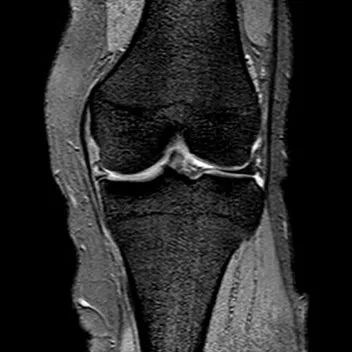

桶柄状撕裂MRI表现

1、宽度减小,在通过半月板体部的冠状面上蝶形消失,同时可见内移的半月板位于髁间窝、交叉韧带旁2、矢状面示残余的前角或后角变小或截断3、半月板前(后)角增宽或双半月板前(后)角征4、双前交叉韧带或双后交叉韧带征

桶柄状撕裂:宽度减小,在通过半月板体部的冠状面上蝶形消失,同时可见内移的半月板位于髁间窝、交叉韧带旁